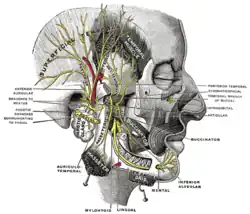

Der Nervus alveolaris inferior („Nerv der Unterkieferzahnfächer“) ist ein Abzweig des Nervus mandibularis („Unterkiefernerv“), welcher wiederum ein Ast des fünften Hirnnerven (Nervus trigeminus) ist.

Der Nervus alveolaris inferior tritt durch das Foramen mandibulae (Unterkieferloch) in den Unterkieferknochen ein. Hier verläuft er in einem Knochenkanal (Canalis mandibulae) kinnwärts und gibt jeweils Äste (Rami alveolares) an die Zähne des Unterkiefers ab.

Der Endast des Nervus alveolaris inferior tritt am Foramen mentale aus dem Unterkieferknochen aus. Dieser wird als Nervus mentalis („Kinnnerv“) bezeichnet und versorgt die Haut des Kinns und die Unterlippe.

Sowohl am Foramen mandibulae (→ Leitungsanästhesie am Foramen mandibulae) als auch Foramen mentale ist eine Leitungsanästhesie des Nerven zur Schmerzausschaltung bei Zahnbehandlungen möglich.